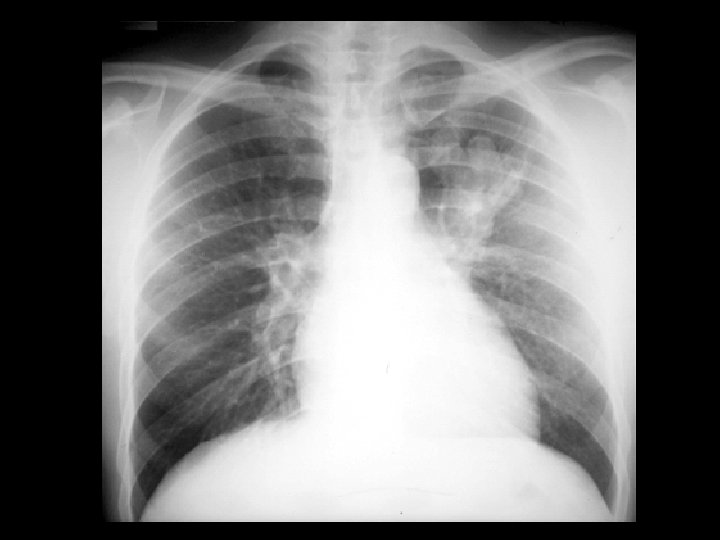

Swyer-James syndrome • Findings: – Hyperlucent left lung – Diminished pulmonary parenchymal and vascular markings – Expiration view shows air trapping • ddx: – Endobronhial foreign body – Pneumothorax – Congenital lobar emphysema – Pulomary artery hypoplasia